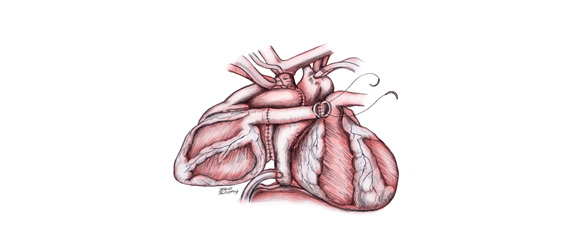

一、正位心臟移植手術:

捐贈者心臟送達後,開始進行低溫體外循環;將主動脈之近端夾住,並將上下腔動脈用帶子勒緊,將原本心臟摘除;將捐贈者心臟之心房部分稍加修整後進行縫合, 縫合由左心房之左側開始,分成上下2端進行。 待所有心房皆縫合完畢,即可修整主動脈與肺動脈之長度,結束後打開主動脈夾升高體溫,讓心臟恢復跳動,待體溫回復至36℃停止體外循環,關閉胸骨及傷口手術即完成。